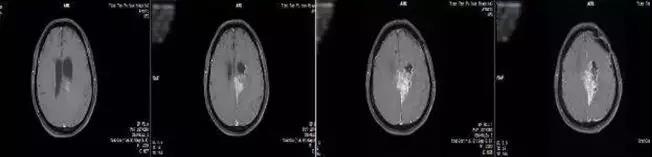

治疗前

治疗一个月后复查,病情缓解